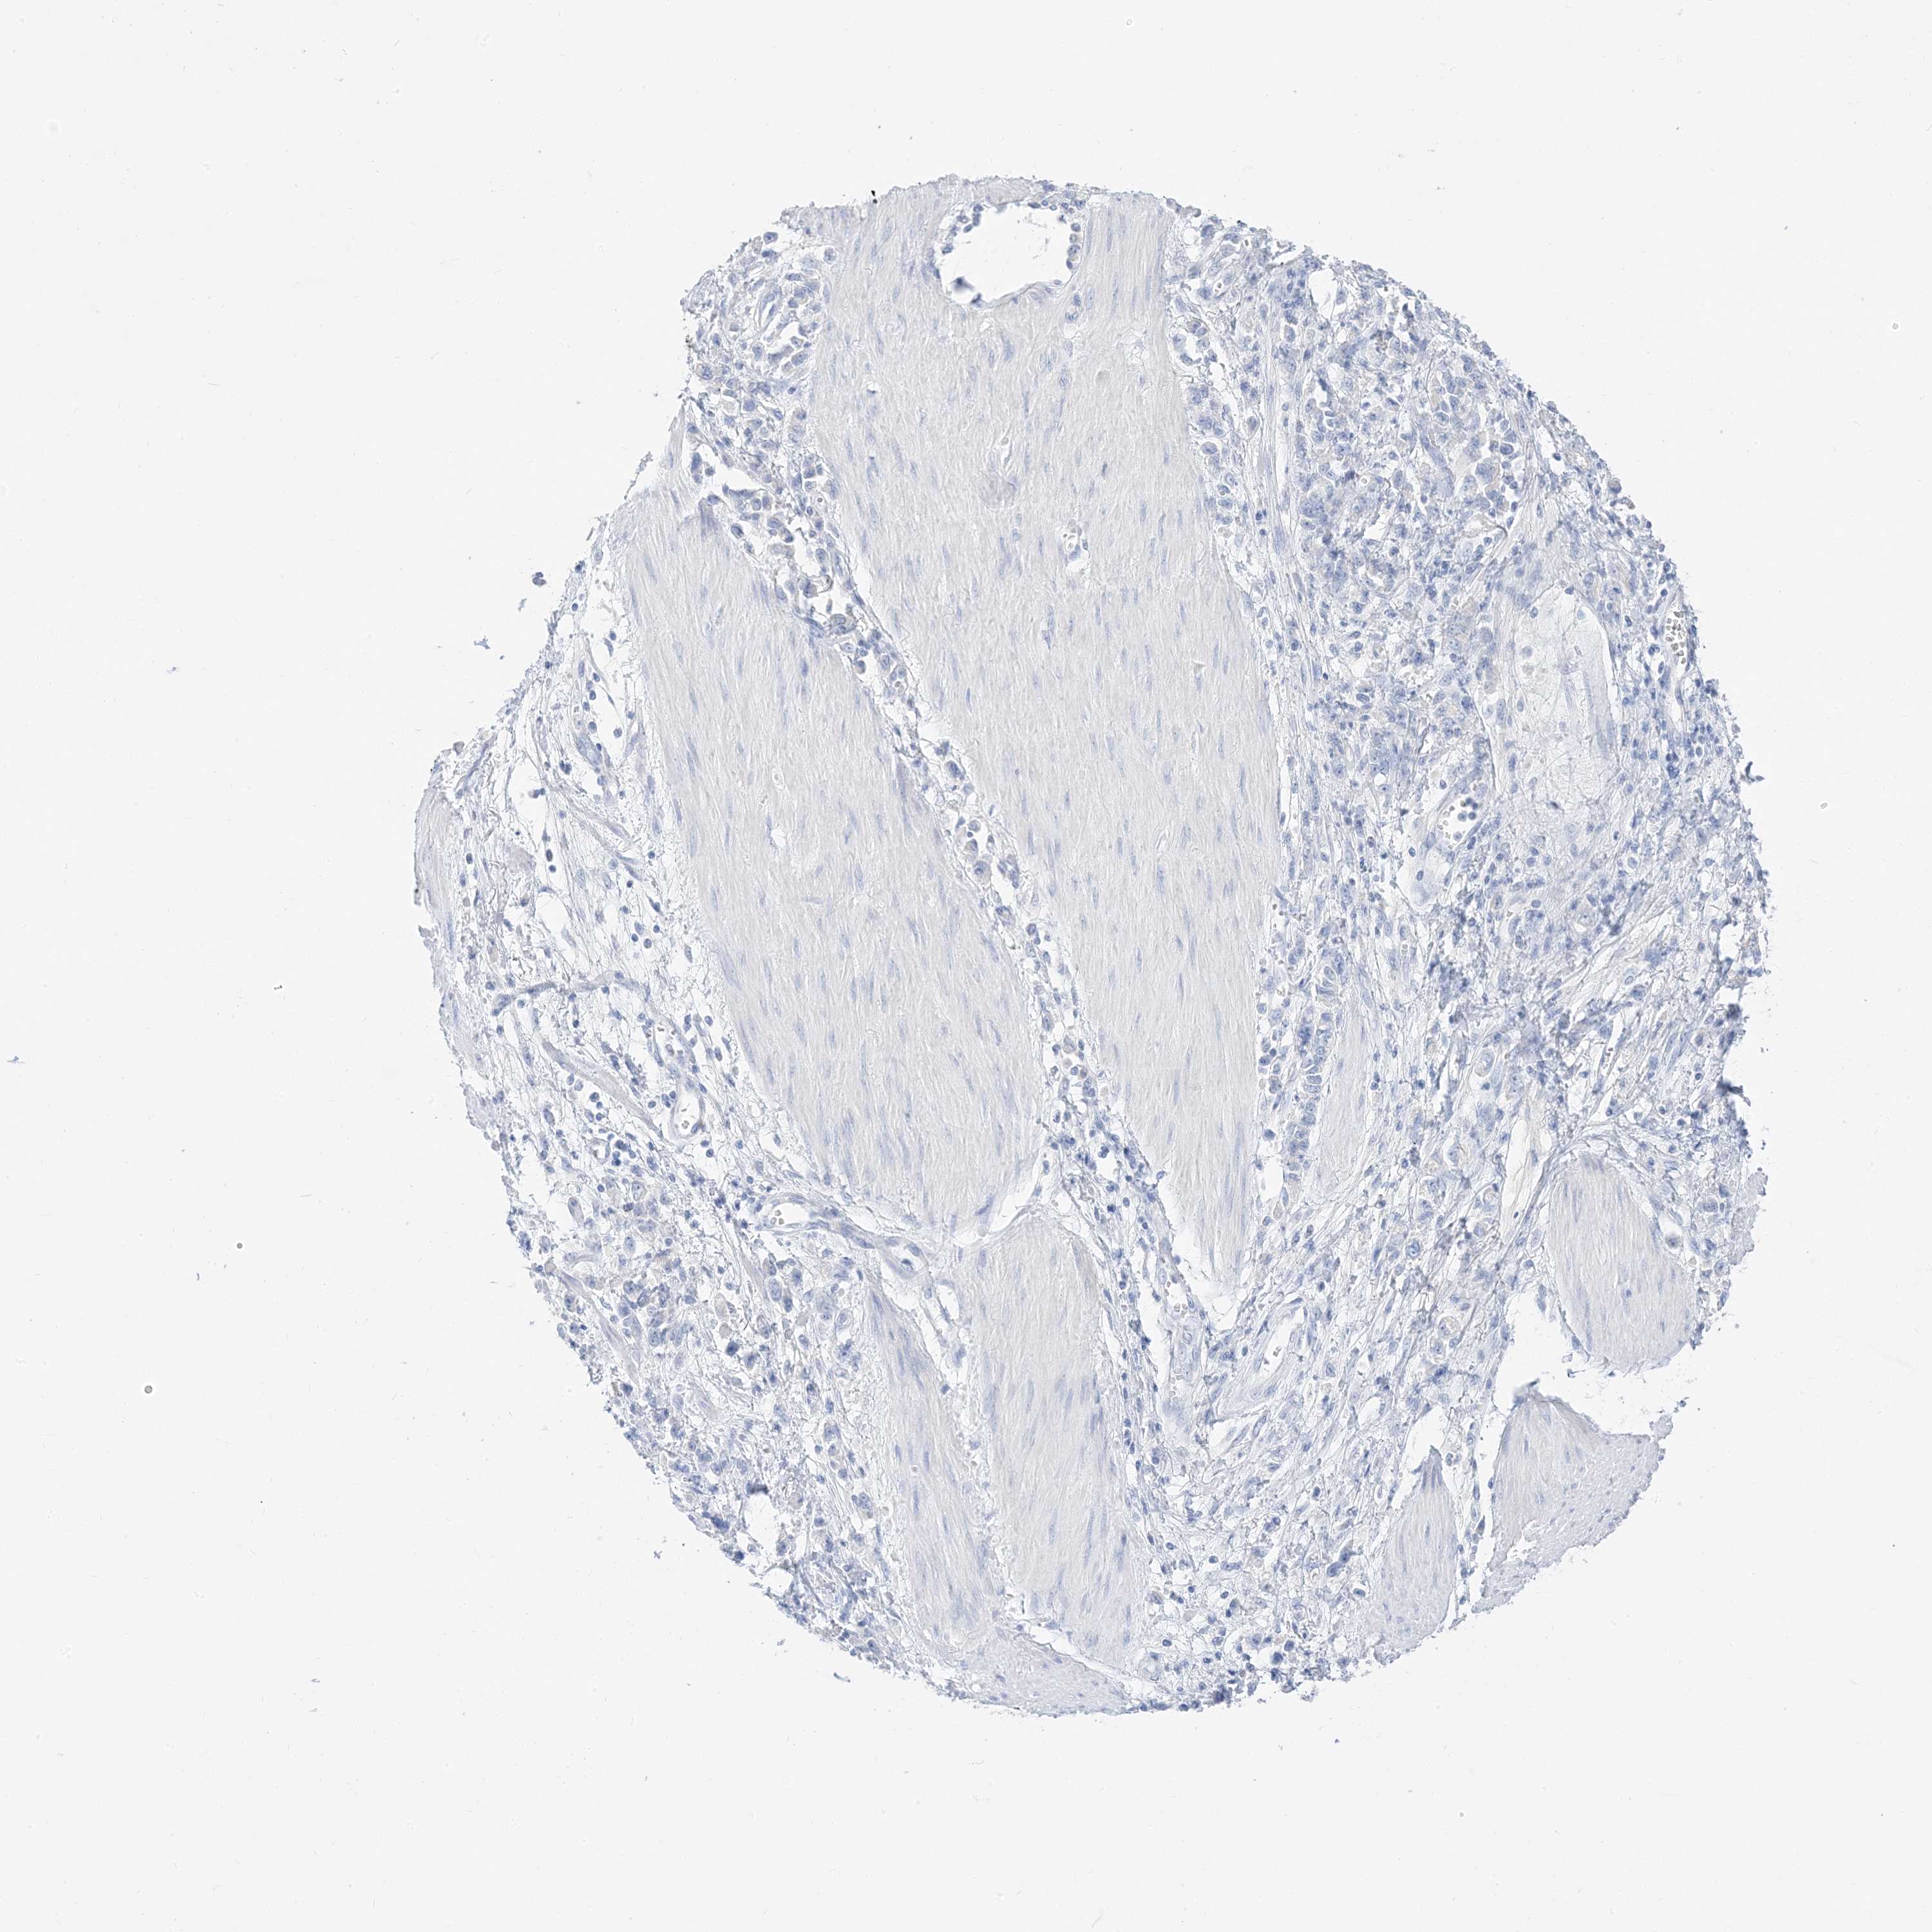

STOMACH CANCER - Protein expressioni

A mouse-over function shows sample information and annotation data. Click on an image to view it in a full screen mode. Samples can be filtered based on level of antibody staining by selecting one or several of the following categories: high, medium, low and not detected. The assay and annotation is described here.

Note that samples used for immunohistochemistry by the Human Protein Atlas do not correspond to samples in the TCGA dataset.

Antibody stainingi

Antibody staining in the annotated cell types in the current human tissue is reported as not detected, low, medium, or high, based on conventional immunohistochemistry profiling in selected tissues. This score is based on the combination of the staining intensity and fraction of stained cells.

Each image is clickable and will lead to virtual microscopy that enables deeper exploration of all samples and also displays staining intensity scores, fraction scores and subcellular localization as well as patient and tissue information for each sample.

Antibody HPA031634

Antibody CAB080501

Antibody CAB080502

Antibody CAB080503

Adenocarcinoma, NOS

Adenocarcinoma, High grade